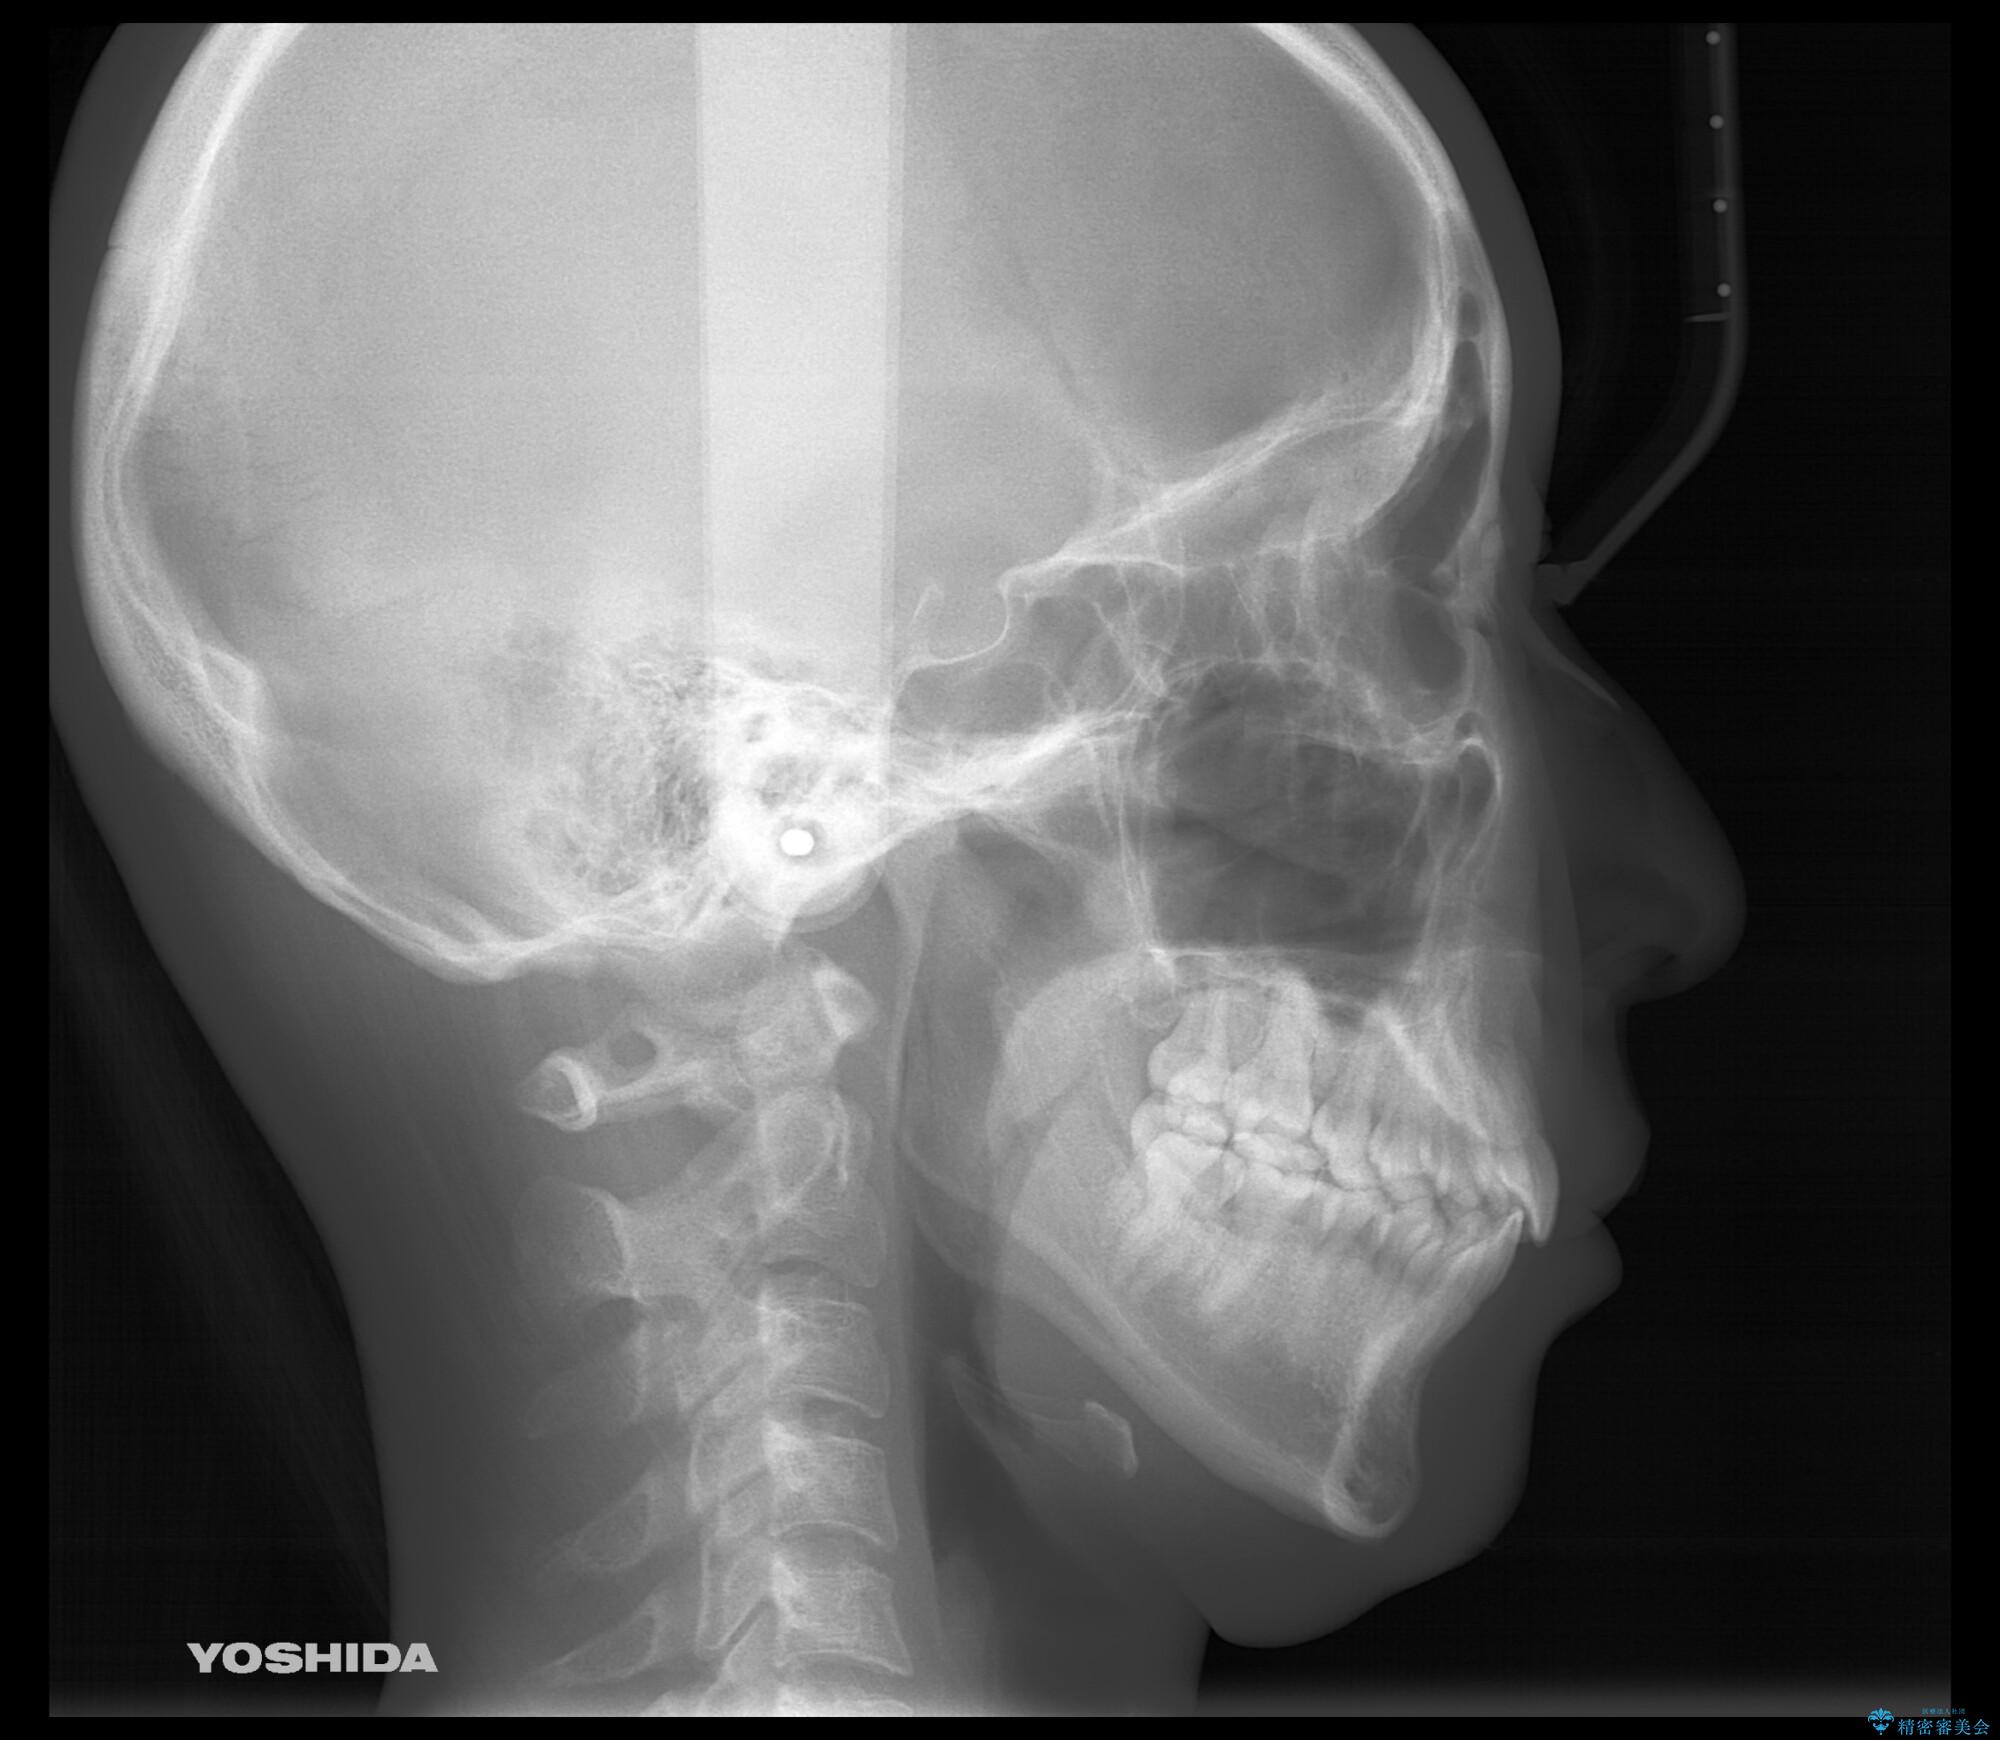

- 前歯のがたつきが気になるとご相談にいらした患者様です。矯正検査の結果、骨格的なズレが大きかったため当初の治療計画では外科矯正をご案内しました。ご本人が手術を望んでおらず、可能な限りの改善を目指すことを目標に治療を開始しました。

元々の骨格的なズレが大きかったため、当初は外科矯正をご提案していました。患者様の強いご希望により、非外科的な処置のみで可及的な改善を目指すことを目標に治療を行いました。以前よりもしっかり噛めるようになり、見た目も劇的に改善したことで大変ご満足いただけました。